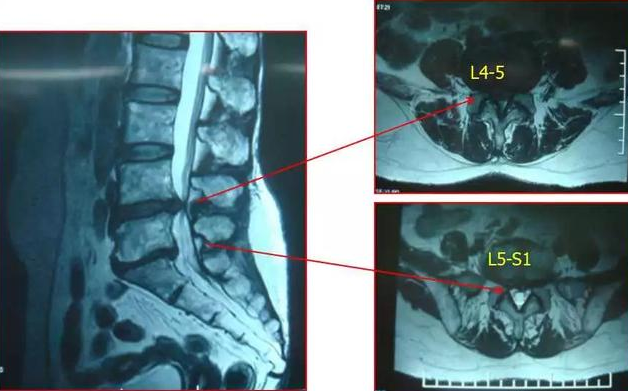

是指腰椎间盘各部分(髓核、纤维环及软骨板)发生退行性改变,在外力因素作用下,椎间盘的纤维环破裂,髓核组织从破裂之处突出(或脱出)即为腰椎间盘突出。

从这里定义看出,腰椎间盘突出只是一个临床影像学诊断,是CT、MRI等呈现腰椎间盘突出或膨出的客观影像,只能说明腰椎间盘发生了变化,如果没有引起相对应的临床症状,就不能说是“腰椎间盘突出症”这个“有病”的结论。所以腰椎间盘突出不是病。

答案是否定的。如果突出量较大,但是没有症状的“健康人”或初次发作者不一定都要选择手术。姜宏认为,单纯影像学上巨大的突出并不是手术指征,合并有疼痛及神经功能的损害才是决定手术与否的关键因素。曾经有巨大腰椎间盘突出非手术治疗后被吸收的病案报道。但是并不是所有的突出患者都能吸收,个人体会,对于大椎管、无终板炎、初次发作以及年轻患者可以吸收的几率较大。